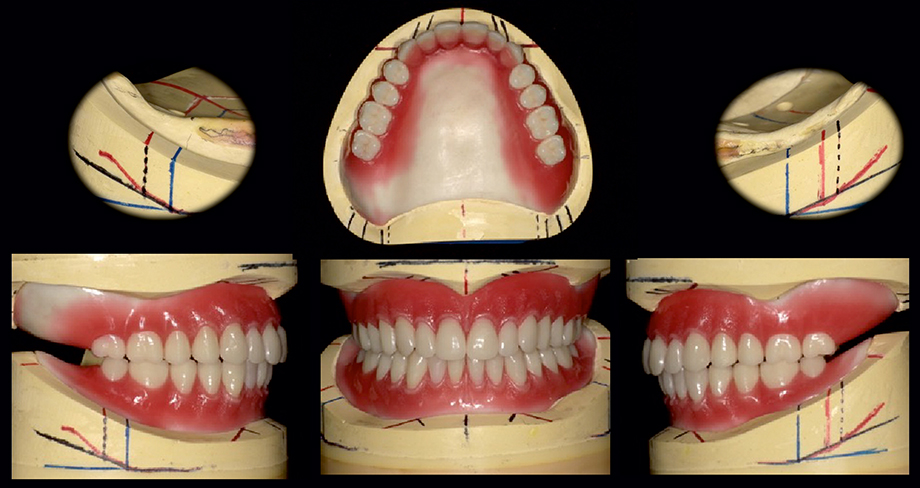

In the United States dental equipment market, cosmetic dentistry represents a flourishing segment, mirroring the escalating desire for aesthetic enhancements and smile transformations. Technological breakthroughs in the field, including digital imaging, CAD/CAM systems, and 3D printing, have brought about a revolution in dental practices, empowering practitioners to offer treatments that are more precise and efficient, which are more comfortable for patients. Furthermore, the United States dental equipment market is characterized by a mounting awareness of oral health's significance. A growing number of individuals now grasp the crucial connection between oral health and overall well-being, resulting in a heightened demand for advanced equipment that facilitates preventive and comprehensive care. The surge in awareness is further complemented by the widening accessibility of dental insurance, motivating people to seek regular dental check-ups and treatments.

The growing demand for cosmetic dentistry can be attributed to several factors. There has been a notable cultural shift toward appreciation for aesthetics and appearances, which has generated an amplified demand for treatments such as teeth whitening, veneers, and orthodontic procedures. Consequently, dental practices are adjusting to fulfil the demand by investing in advanced cosmetic dental equipment and state-of-the-art technologies. Digital imaging, CAD/CAM systems, and 3D printing have dramatically improved treatment planning and execution, rendering cosmetic procedures more precise and foreseeable. The trend mirrors economic considerations, as cosmetic dentistry typically represents a profitable niche in the dental sector, thereby attracting increased investment and innovative developments. Consequently, manufacturers are crafting specialized equipment such as chairside milling machines and laser systems to cater to the burgeoning markets.